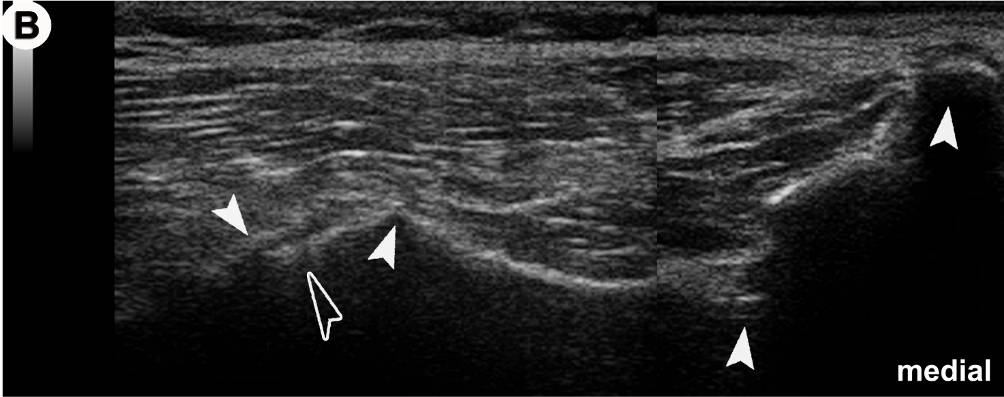

Anatomischer Transversalschnitt (A) und korrespondierendes US-Bild (B) auf Ebene des Foramen sacrale posterius secundum (II): Grundlage für die US-gezielte Injektion des Iliosakralgelenkes (ISG).

In der US-Darstellung ist der dorsalste Anteil des ISG einsehbar (offener Pfeilkopf). Der Spalt entspricht dem radiologischen Gelenkspalt! Die knöchernen Landmarken (gefüllte Pfeilköpfe) sind aber in allen Details deutlich zu erkennen (von medial nach lateral): Crista sacralis mediana, II, Crista sacralis lateralis, Facies glutea ossis ilii.